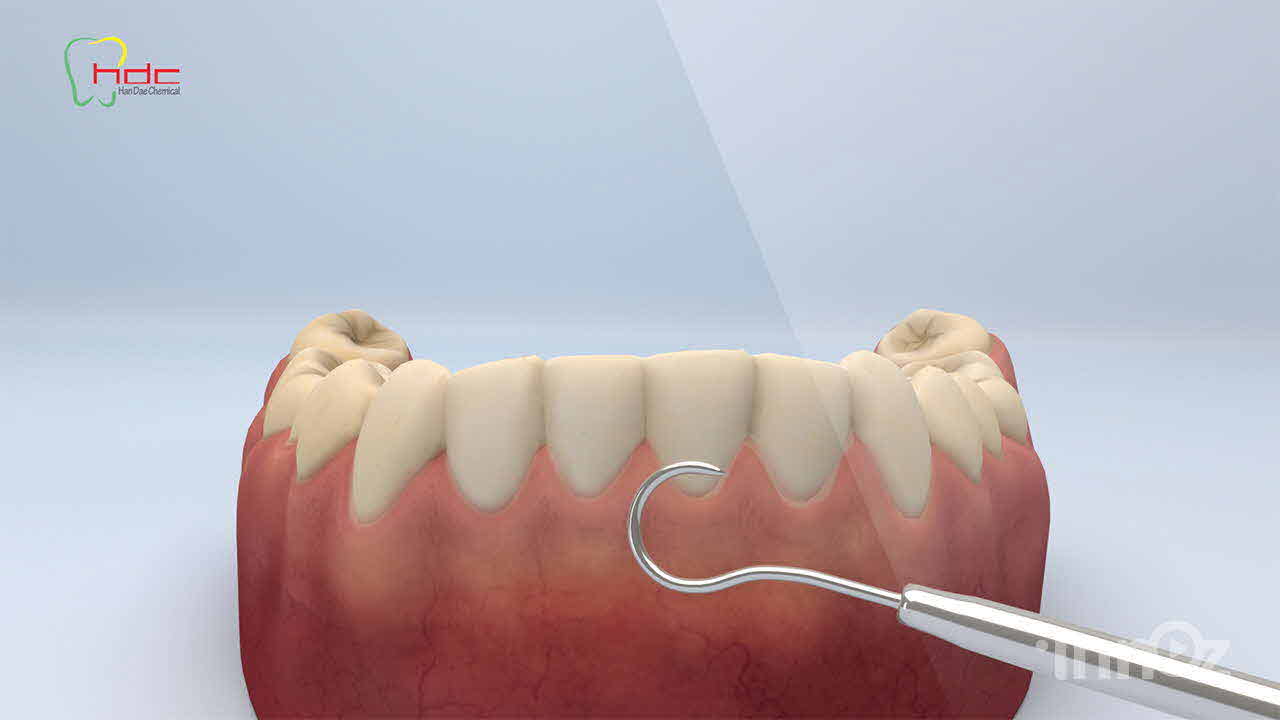

한대케미칼

치과의료기기 전문기업

치과의료기기 전문기업

치과의료기기 전문기업